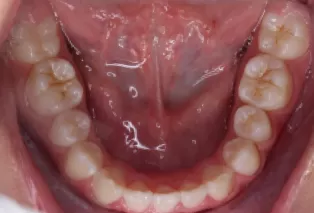

Intraoral photos